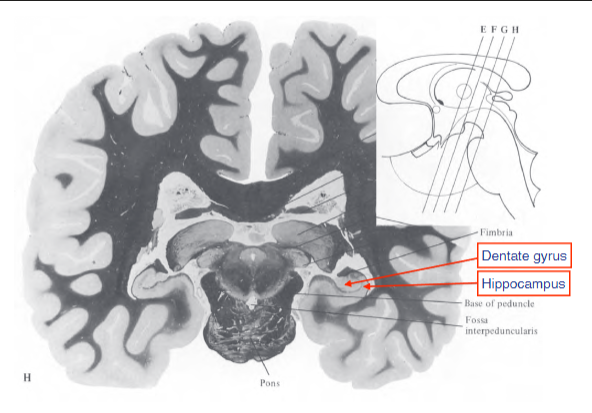

describe the hippocampus?

found posteriorly to the amygdala, involved in encoding declarative memories

describe the location of the dentate gyrus.

connected to hippocampal formation